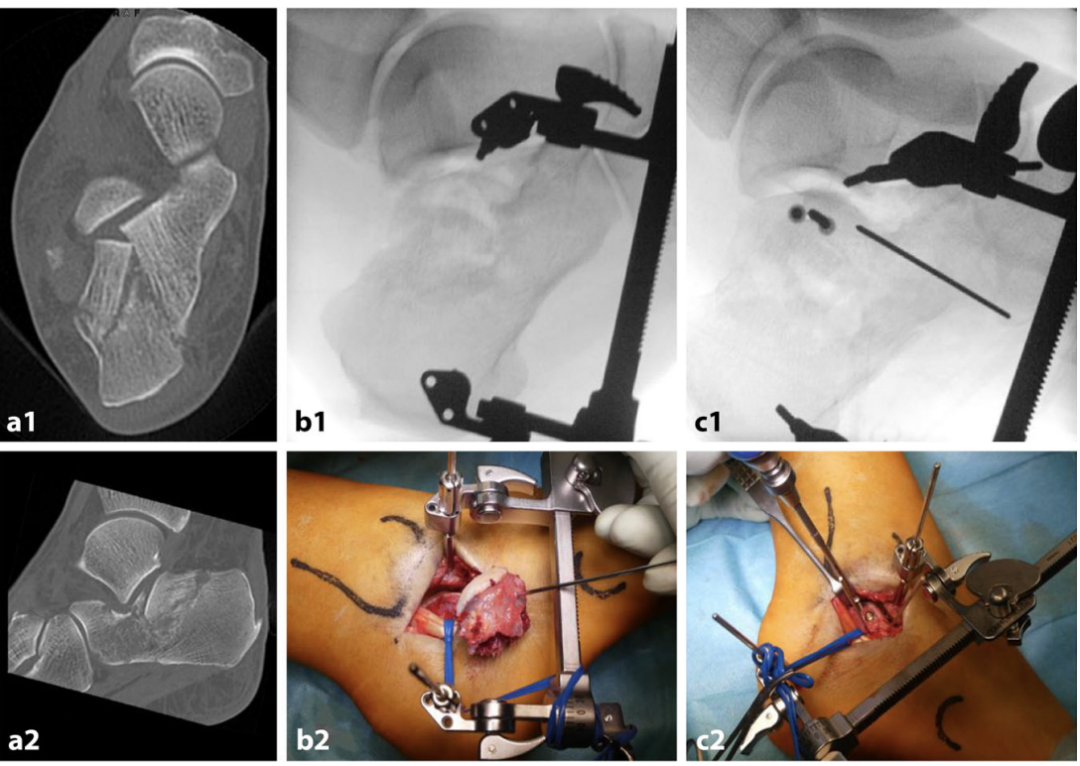

第一步为跟骨结节骨块的牵开复位,该大背侧主骨块通常呈嵌插与外翻畸形。本步骤的目的是解除骨块嵌插,为关节面骨块的操作创造无阻碍的复位空间。

借助经皮置入的带 T 型手柄的斯氏针,采用摇杆技术对跟骨结节骨块进行可控操作,术中可将Böhler角的矫正情况作为复位参考指标。复位后的跟骨结节骨块需用克氏针临时固定于通常较为稳定的内侧载距突骨块(恒定骨块)。亦可采用骨撬进行复位,沿骨折线置入骨撬,沿骨折缝隙轻柔撬拨,精准松解并将跟骨结节复位至内侧壁。

操作技巧

可使用牵开器复位跟骨结节骨块:在距骨外侧突与跟骨结节处分别置入克氏针,利用牵开器可三维调节的连接杆,可控地恢复跟骨高度、矫正后足畸形,并解除关节面骨块的嵌插。牵开器可使骨折块在矫正位置保持稳定固定,为后续重建操作提供条件。